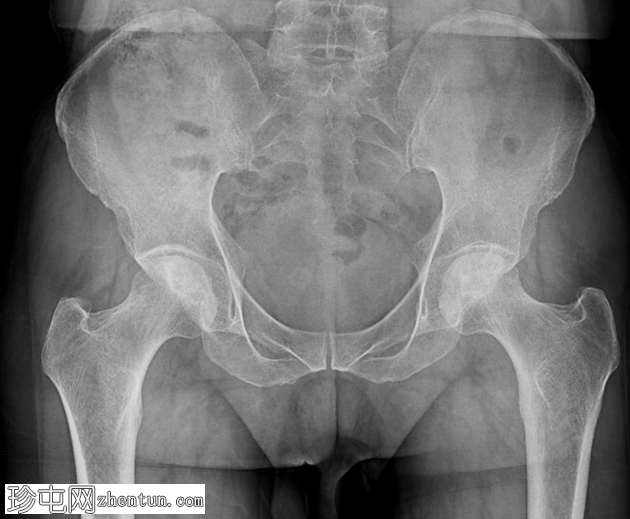

X线片

正位片

骨盆及双侧髋关节(前后位)

双侧股骨头均可见硬化区域,间杂透亮区。双侧可见可疑的软骨下透亮线(新月征)。髋关节间隙相对完整。未见明显的继发性骨关节炎改变。未见急性骨折或脱位。